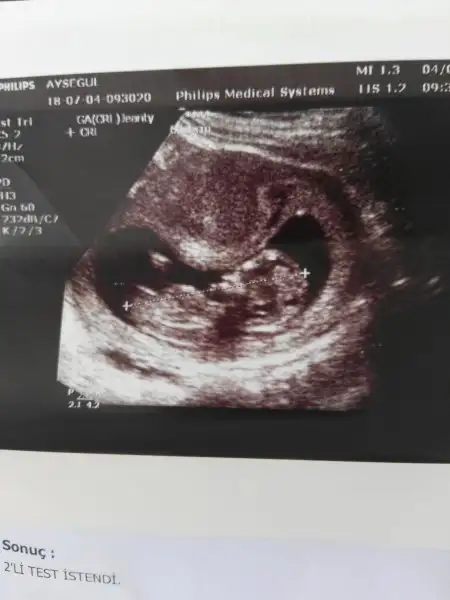

Eki Görüntüle 2164979 Kızlar ikili test için gittik, bebek yatıyordu, Dr. Biraz cihazı bastırınca görüntü değişiyordu ama bebek mi hareket ediyordu cihaz mi görüntü degistiyor anlamıyorum

Dr. Apış arasına baktı üçlü cizli gösterdi %80 kız ama, sanki yukarda bir cikinti da gördüm yanılıyor olabilirim de dedi.

Geçen hafta gittigimizde de bebek hareket etmiyordu soraydim keşke çıkınca düştü

Dr. Profosordu ama bir sıkıntı olsa derdi herhalde ve yanilmamistir bence, ben erkek hissetsem de kim görse kıza benzyor diyor,bakalım hayırlısı artık